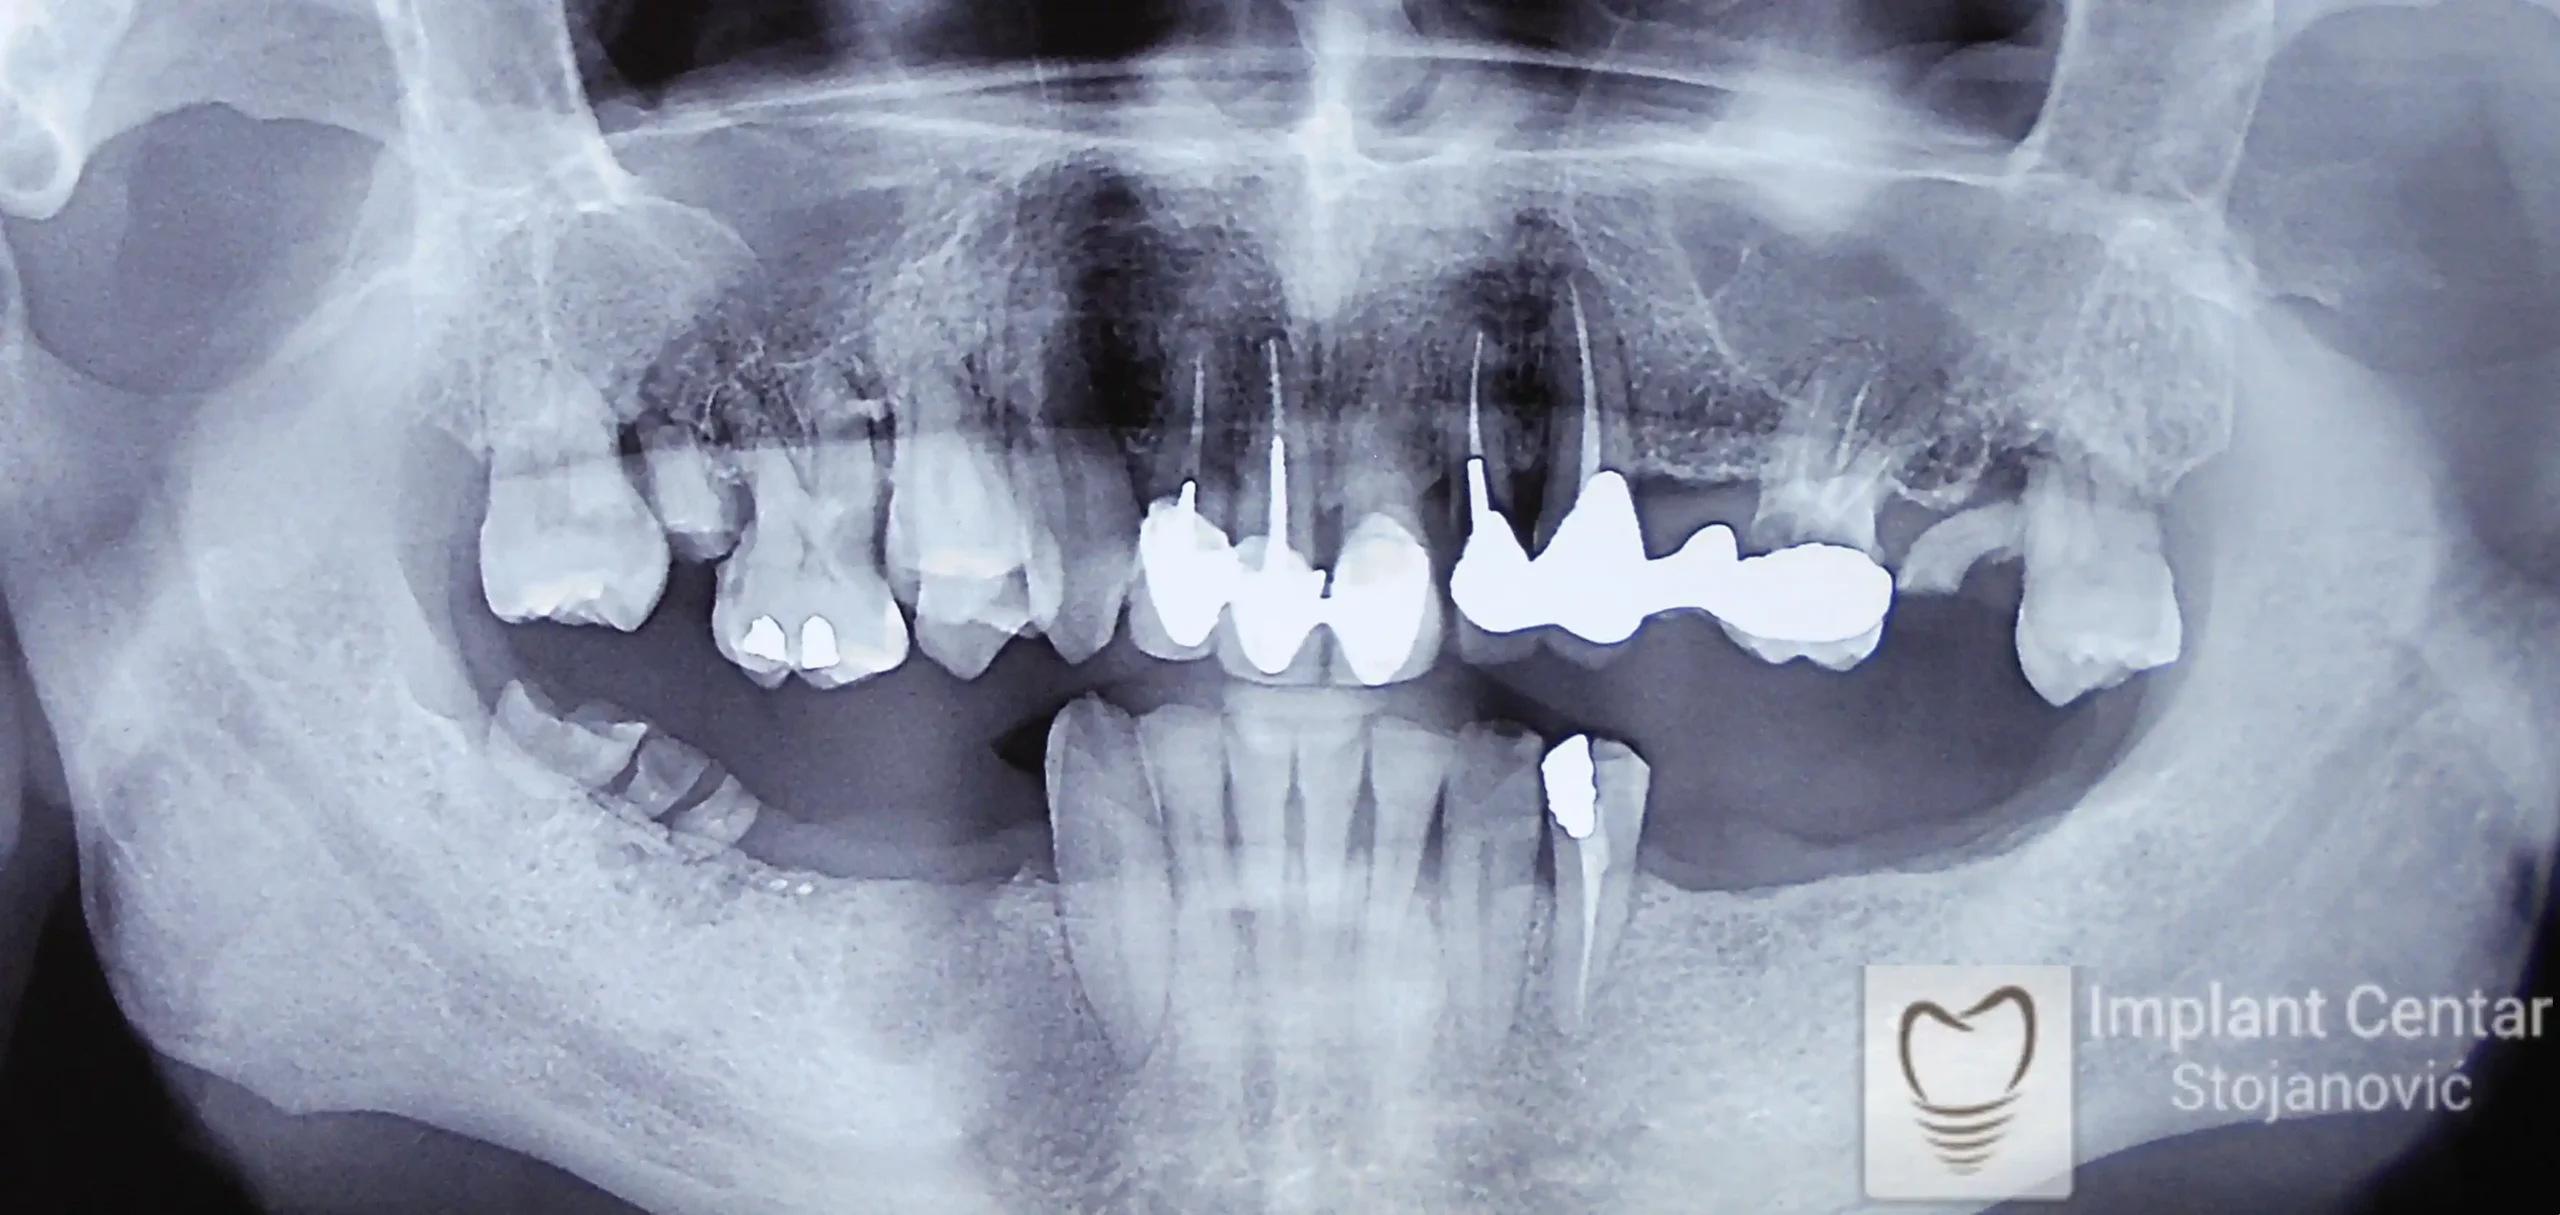

Na slici 1. i slici 2. prikazan je izgled pacijenta pre početka terapije – klinički i rendgenološki.

Nakon vađenja zuba, ugrađeni su implantati. Na slici 3 prikazan je ortopan snimak sa ugrđenim implantatima. Tokom perioda osteointegracije, pacijent je bio zbrinut fiksnim privremenim krunicama na implantatima, koje su izrađene samo dva dana nakon hirurške intervencije.